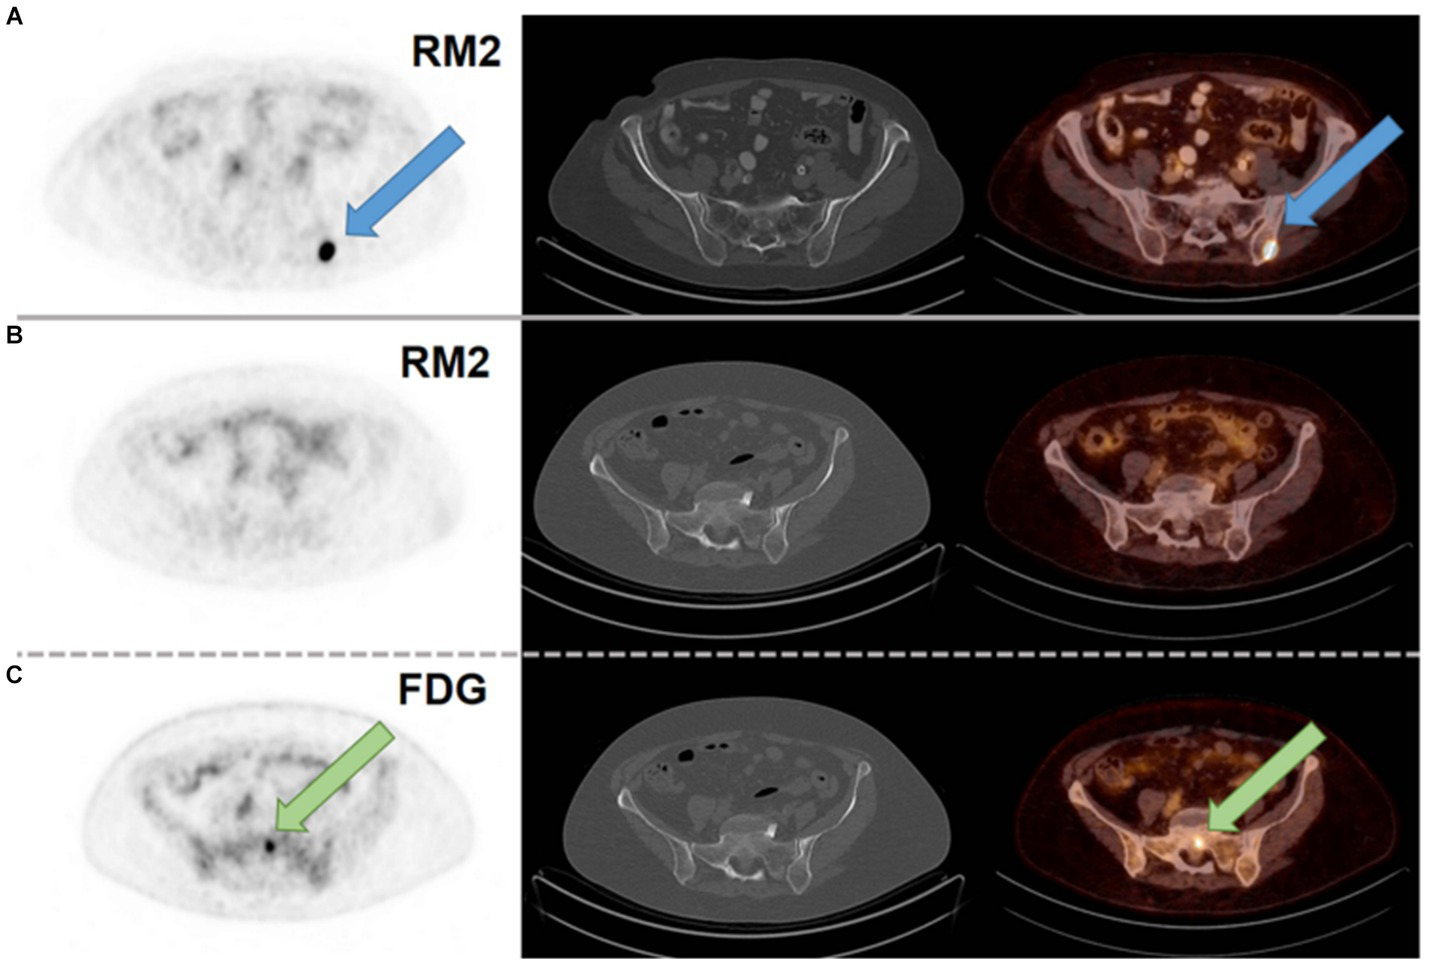

Another study reported in 2021, describes the use of [68Ga]Ga-RM2 (Figure 6, 8) for PET/CT tumor visualization in patients with pre-treated, ER-positive BC and suspected metastases. The pilot study included 8 patients with initial ER-positive and pre-treated BC. Seven of the 8 patients were still in treatment with endocrine therapy. In 6 patients, a strong tracer uptake was observed in all metastatic lesions while no uptake was observed in the other two patients, as shown in Figure 11. These results suggest that [68Ga]Ga-RM2 imaging could support treatment decision in the majority of patients with advanced disease stage of pre-treated ER-positive BC (102).

Figure 11

(A) [68Ga]Ga-RM2 PET/CT of a patient with a metastasis in the left iliac bone with intense RM2 binding and not seen on CT (blue arrow; SUVmax 32.1). (B) [68Ga]Ga-RM2 PET/CT of a patient with a bone metastasis in the sacrum without RM2 binding and not seen on CT (SUVmax 1.5; second row). (C) [18F]FDG PET/CT of the same patient with intense hypermetabolism in the sacrum (green arrow; SUVmax 5.8; third row). Axial slices of PET scans (first column), CT scans (second column) and fusion images (third column). Reprinted from Gastrin-Releasing Peptide Receptor Antagonist [68Ga]RM2 PET/CT for Staging of Pre-Treated, Metastasized Breast Cancer by Michalski et al. (102), under Creative Commons Attribution (CC BY) license.